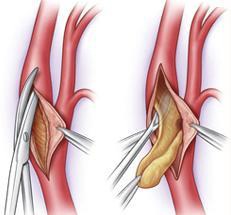

- Ενδαρτηρεκτομή της καρωτίδας

Ενδαρτηρεκτομή καρωτίδας

Πρόκειται για επέμβαση που γίνεται συνήθως με γενική αναισθησία, με μικρή τομή στον τράχηλο. Παρασκευάζεται η καρωτίδα, διανοίγεται, αφαιρείται η αθηρωματική πλάκα και στη συνέχεια συγκλείεται έίτε άμεσα είτε με χρησιμοποίηση ενός εμβαλώματος (patch).

Η διάρκεια της είναι συνήθως 1 – 2ώρες και η πιθανότητα σοβαρών επιπλοκών (εγκεφαλικό, έμφραγμα μυοκαρδίου) είναι μικρότερη από 3%. Λιγότερο σοβαρή και συνήθως παροδική επιπλοκή είναι η βλάβη νεύρων της περιοχής.